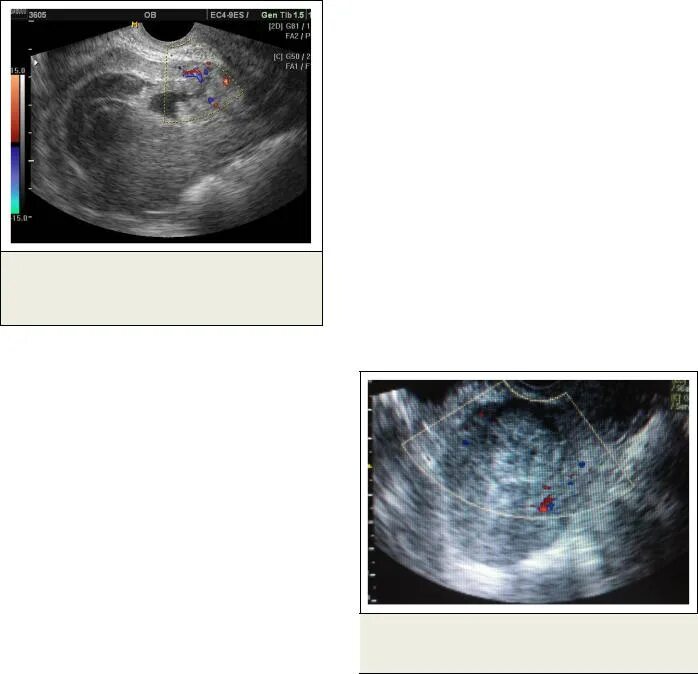

Гематометра симптомы